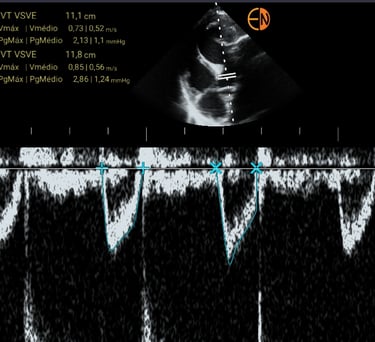

POCUS Cardíaco - medidas: Avaliação quantitativa do débito cardíaco, volume sistólico e função sistólica dos ventrículos.